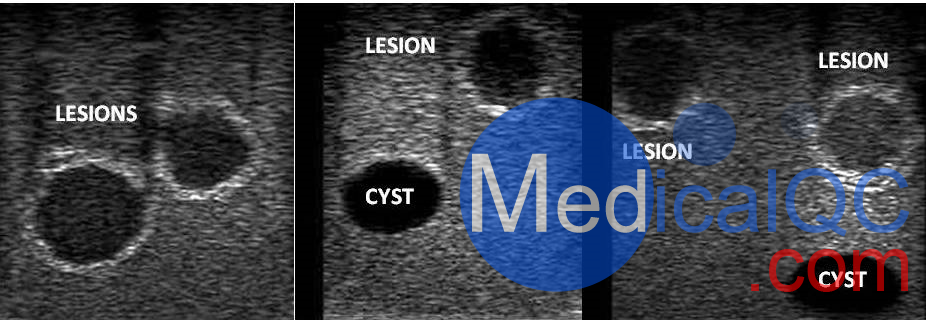

乳腺模體超聲圖像(病變和囊腫)

WEK-YMBP多功能乳腺模體,WEK-YMBP乳腺模體超聲圖像